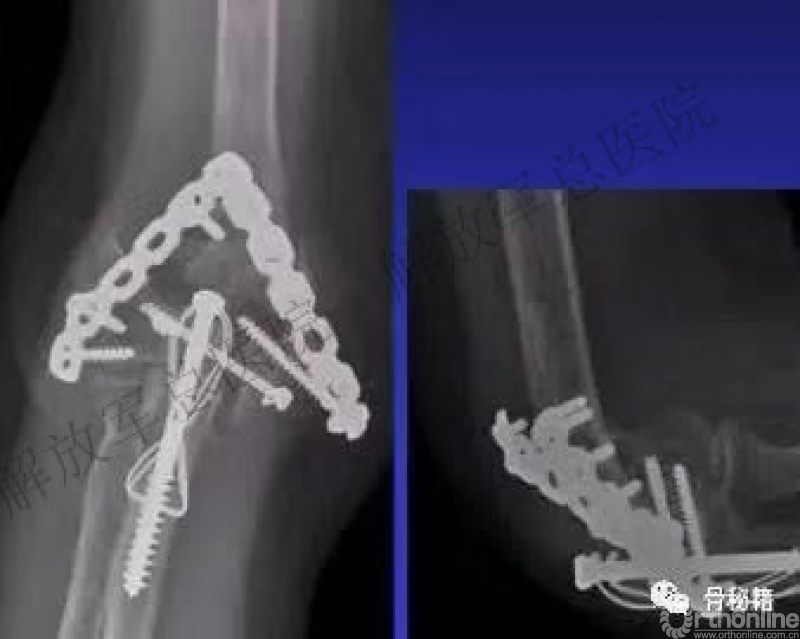

1.复位时,先把滑车固定好,可应用空心螺钉。

2.然后用克氏针将骨折块经过钢板来进行固定,注意钢板一定要把远端包裹一点。

3.先用普通螺钉固定肱骨近端的孔,完成临时固定,不用拧太紧。

4.然后进行远端的单侧加压固定。

5.应用大巾钳和加压螺钉完成髁间的加压固定。

具体办法:用大巾钳完成两侧柱的加压后应用螺钉完成固定。

6.同样的方法完成对侧的固定。

7.最后完成其他的螺钉锁定,形成一个完整的肱骨远端力学结构。

远端螺钉尽量打满,完成髁间的链接,近端3个以上螺钉。

髁间一定要有链接的长螺钉(对角线螺钉)。